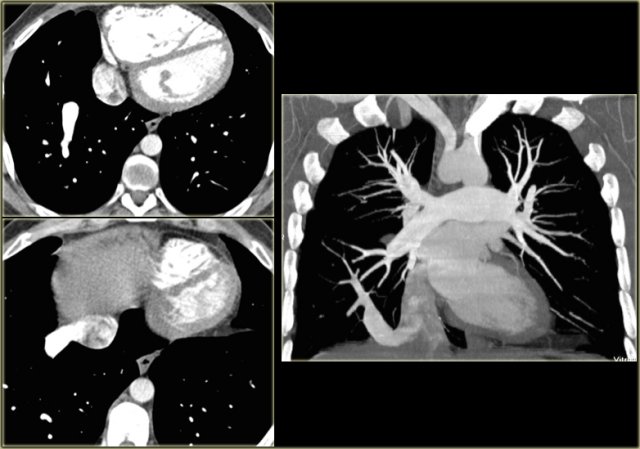

Axial image and volume rendering posterior view Axial image and volume rendering posterior view

Right Arch Mirror Image

This is the mirror-image variety of the left arch.

On the left a 2 year old girl with wheezing and coughing.

On the axial image there is a right arch

On the volume rendered image there is mirror image branching of the brachiocephalic arteries, no aberrant subclavian artery, so this is a right arch mirror image.

Mirror image aortic arch (yellow arrow) and a VSD (red arrow) Mirror image aortic arch (yellow arrow) and a VSD (red arrow)

This anomaly is asymptomatic, because there is no obstructing ring.

Almost all of these patients however come to our attention because they have associated congenital heart disease in 98% of cases.

This patient had a mirror image aortic arch and a VSD.

Mirror image aortic arch in patient operated for tetralogy of Fallot. Mirror image aortic arch in patient operated for tetralogy of Fallot.

On the left an adult who was operated in his childhood for a Tetralogy of Fallot (pulmonary stenosis, right ventricular hypertrophy, VSD, overriding aorta).

At surgery the VSD was patched and the pulmonary outflow tract was enlarged.

Notice that there is also a right arch.